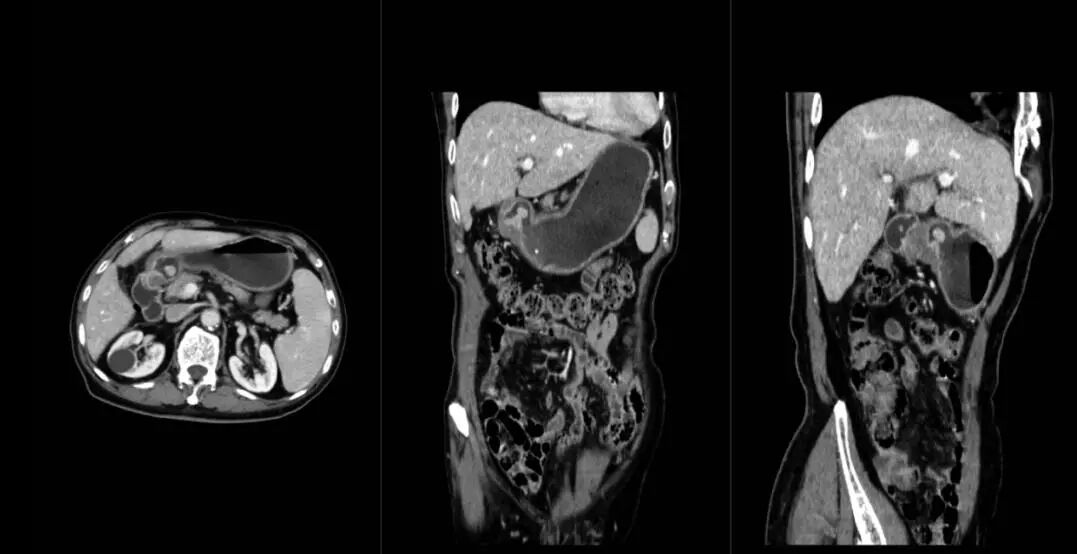

5、腹部高清成像:了解腹腔脏器有无感染性疾病,如:炎症、结核、脓肿等;有无占位,如良、恶性肿瘤,转移性肿瘤等;有无畸形、结石、梗阻、穿孔、积液等。

联影ct怎么样【医讯】勐腊县人民医院引进国产联影高端64排128层螺旋CT正式投入使用_https://www.jmylbn.com_新闻资讯_第9张